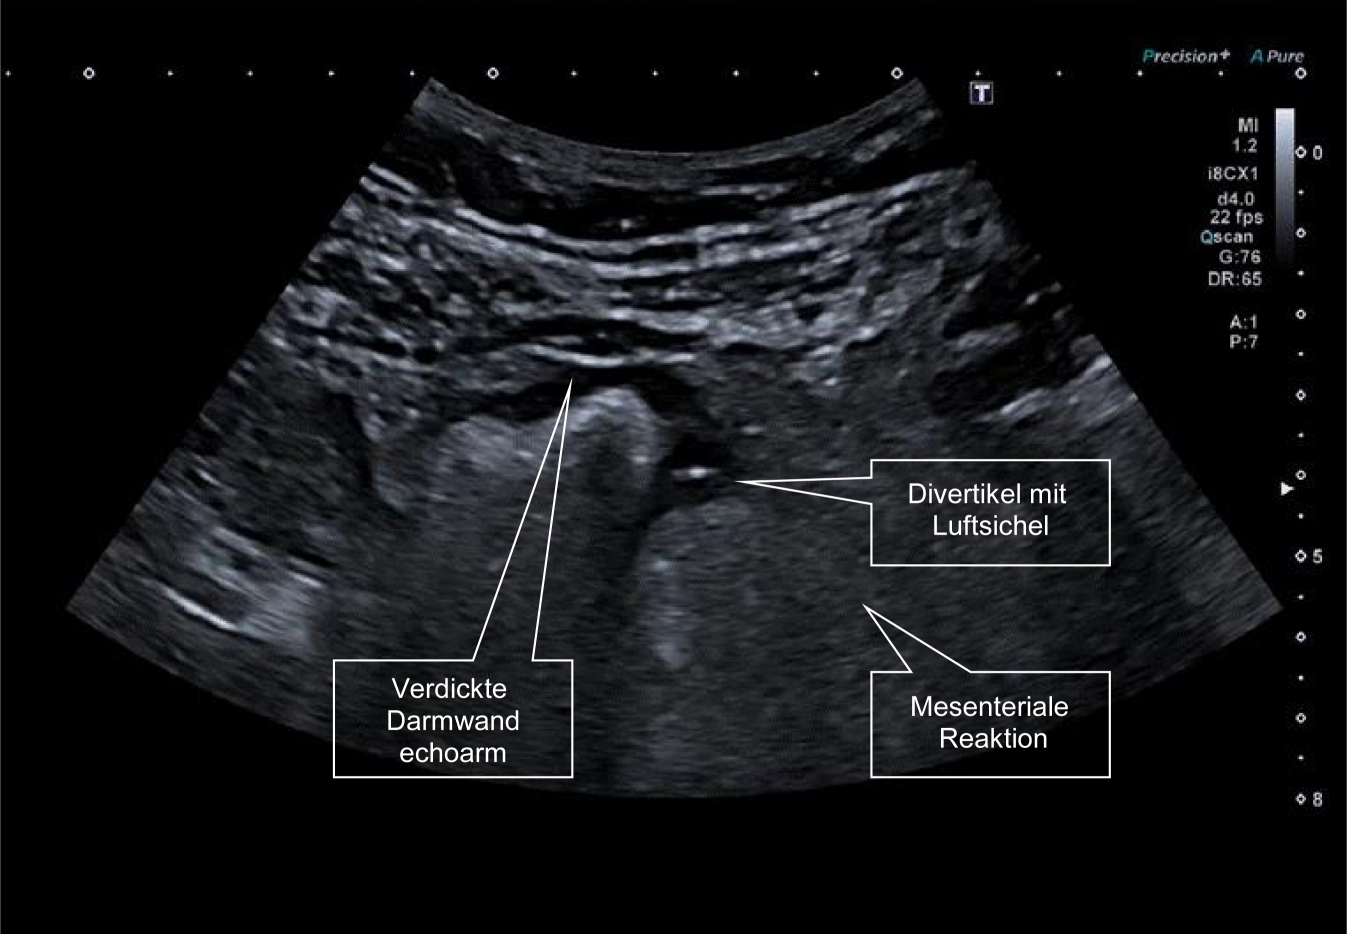

Auch bei V. a. eine akute Divertikulitis wird der Ultraschall als diagnostisches Verfahren in den aktuellen Leitlinien empfohlen. Sowohl Ultraschall wie auch CT ermöglichen durch die Darstellung des Darms und der extraluminalen Strukturen eine umfassende differenzialdiagnostische Beurteilung (Abb. 2). Dies ist in Statement 4.7 der AWMF-Leitlinie klar dargestellt [6, 7].

Abb. 2

57-jähriger Patient mit neu aufgetretenen Unterbauchschmerzen links und Durchfällen mit 7 Stuhlgängen pro Tag. (Im linken Unterbauch im Bereich des Sigma zeigt sich eine deutliche echoarme Verdickung der Darmwand, ein Divertikel im aktuellen Bild mit Luftreflex und eine deutliche mesenteriale Reaktion um die Entzündung)

Ein grosser Vorteil der Ultraschalluntersuchung ist, dass in Kooperation mit den Patient(inn)en der Punkt des maximalen Schmerzes erfasst werden kann und die Untersuchung zunächst auf diesen Bereich fokussiert werden kann. Häufig ist ein typisches Bild sichtbar mit einer verdickten Darmwand, einer kreisförmigen echoarmen Region nicht selten mit einer Luftsichel und darüber hinaus eine Reaktion des mesenterialen Fettgewebes, die in der Literatur als sogenannte „fibro-fatty proliferation“ bezeichnet wird. Dieses Bild ist assoziiert mit einer Einengung des Darmlumens. Bei Ausbildung von Komplikationen wird man zudem Abszessformationen oder freie Flüssigkeit im kleinen Becken nach einer Perforation beobachten können. Bei einer Perforation kann darüber hinaus in Rückenlage freie Luft gefunden werden. Darüber hinaus ist das Zeichen der Entzündung ein verstärktes Gefässecho häufig sichtbar.